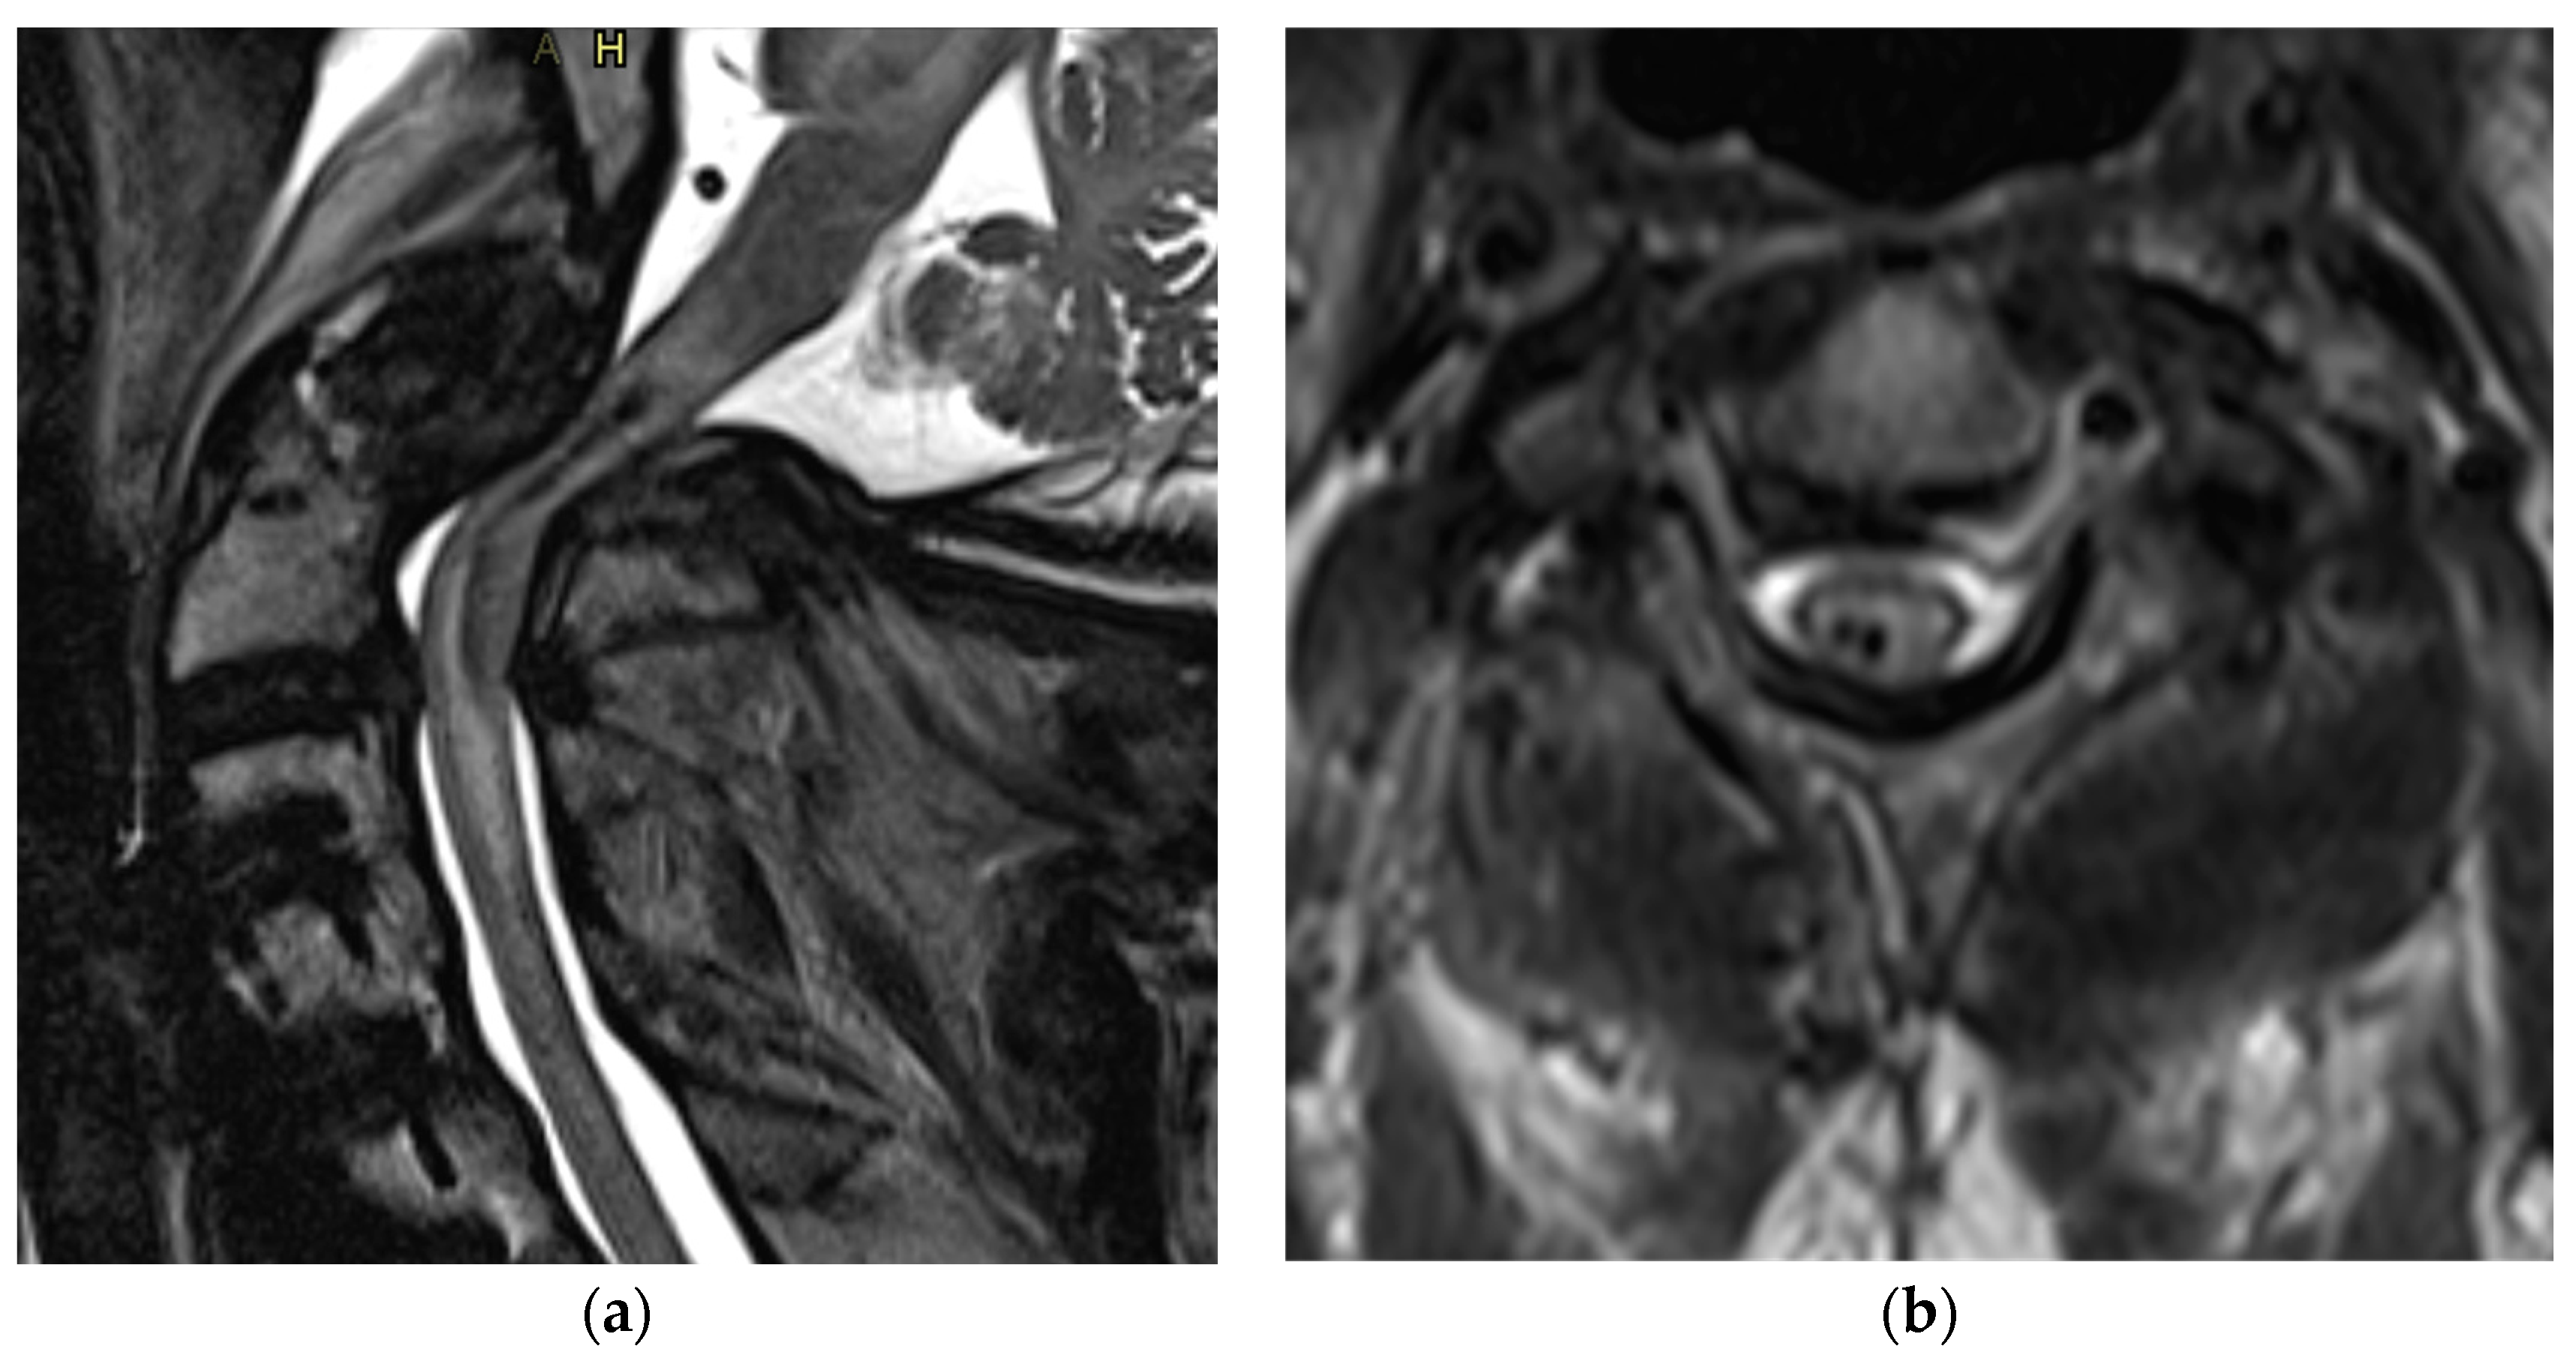

Figure 5.

(a) Sagittal and (b) axial view of T2 MRI showing severe spinal cord injury with intramedullary hemorrhage.

T2-weighted MRI is sensitive to the paramagnetic effects of iron present in blood products. Intramedullary hemorrhage presents as an area of hypo-intensity on T2W imaging, and its presence has a prognostic implication (Figure 4) [28,31,32]. T2*W and susceptibility-weighted imaging (SWI) sequences are also used for the detection of intramedullary hemorrhage [33].